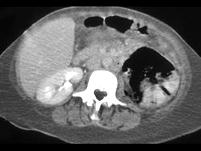

问题 女,63岁,高热、左侧腰痛伴尿频、尿痛,请根据所示图像,选择最可能诊断 ( )

选项 A、慢性肾盂肾炎 B、黄色肉芽肿性肾盂肾炎 C、化脓性肾盂肾炎 D、气肿性肾盂肾炎 E、左肾脓肿

答案 D